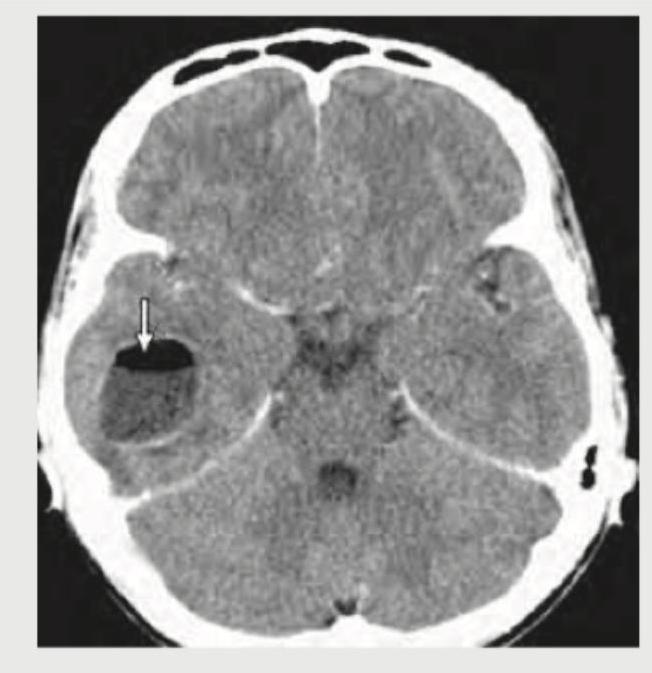

What does the CECT head show?

Explanation: ***Brain abscess*** - The CECT image displays a **hypodense lesion with a well-defined hyperdense rim** after contrast administration, characteristic of a ring-enhancing lesion - The arrow specifically points to a **fluid-level within the lesion**, suggesting a collection of fluid with varying densities, a key feature of pyogenic brain abscess - Brain abscess typically presents with **thick, smooth, and uniform ring enhancement** with a hypodense necrotic center, exactly as seen in this image - The presence of a **fluid-fluid level** is highly suggestive of an abscess with pus and debris layering *Ring enhancing lesion* - While this is a correct **descriptive finding** of what is seen on imaging, it is not the most specific diagnosis - "Ring enhancing lesion" is a **general radiological term** that encompasses multiple pathologies including abscesses, necrotic tumors, metastases, and tuberculomas - In medical education and clinical practice, identifying the **specific diagnosis** (brain abscess) is more valuable than just describing the imaging pattern *Brain infarction* - **Brain infarction** typically appears as a **hypodense area** on CT corresponding to ischemic tissue - Infarcts generally do not show ring enhancement in acute or subacute phases - There is no evidence of **wedge-shaped hypodensity** or vascular territory distribution consistent with infarction *Pneumocephalus* - **Pneumocephalus** refers to the presence of **air within the cranial vault** - Air would appear as sharply demarcated, very low-density (black/hypodense) areas on CT scans - The observed lesion with fluid level and ring enhancement is not consistent with **intracranial air**